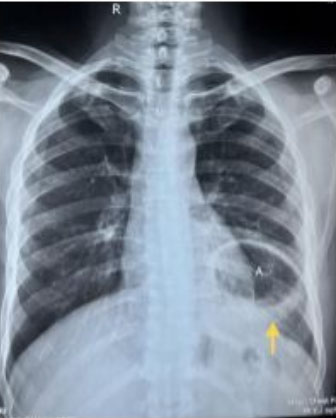

The gastroesophageal junction (GEJ) was in place but the gastro-duodenal junction was displaced supero-laterally on the left. Computed tomography films provided additional information suggestive of rotation of the stomach along its long axis, consistent with a partial gastric volvulus (Figure 1 and Figure 3). Chest X-ray (CXR) posteroanterior (P/A) view in erect posture revealed the position of the fundic gas shadow to be above the left hemi-diaphragm (Figure 4).

Figure 4: CXR posteroanterior view showing the fundic gas shadow (A) above the left dome of the diaphragm (arrow).

Share Image: